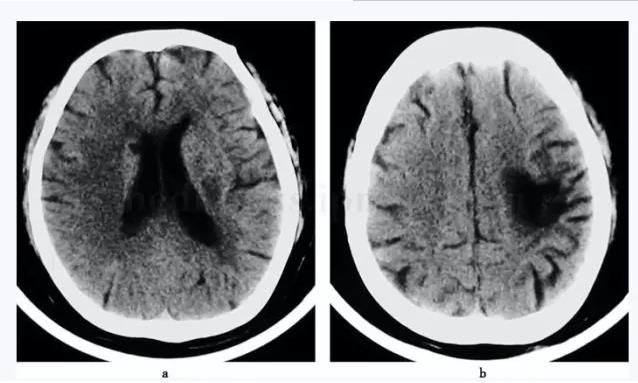

来我院急诊肌内注射苯巴比妥钠100mg,每日1次,口服丙戊酸钠250mg,每日2次,但发作次数逐渐频繁,每次发作持续时间延长。发病第12天以症状性癫痫(部分性发作)收入神经内科癫痫病区。既往精神分裂症病史40余年,长期口服氯丙嗪(100mg,每日1次)、地西泮(5mg,每日1次)、苯海索(20mg,每日1次)。高血压史30年,长期服用北京降压0号(1粒,每日1次)。5年前脑梗死,头颅CT扫描(图8-1)证实(表8-1),未遗留肢体瘫痪;3年前脑出血,头颅CT扫描证实(图8-2),遗留右侧肢体偏瘫。否认癫痫发作史。数年前有甲状腺瘤手术史。

图8-1 头颅CT(2002‐07‐05)双侧脑室旁陈旧腔隙性脑梗死(a),左颞叶陈旧性脑梗死(b)

图8-2 头颅CT(2002‐11‐20)左侧颞叶脑出血,右侧脑室旁腔隙性脑梗死(a)。左颞叶陈旧梗死(b)